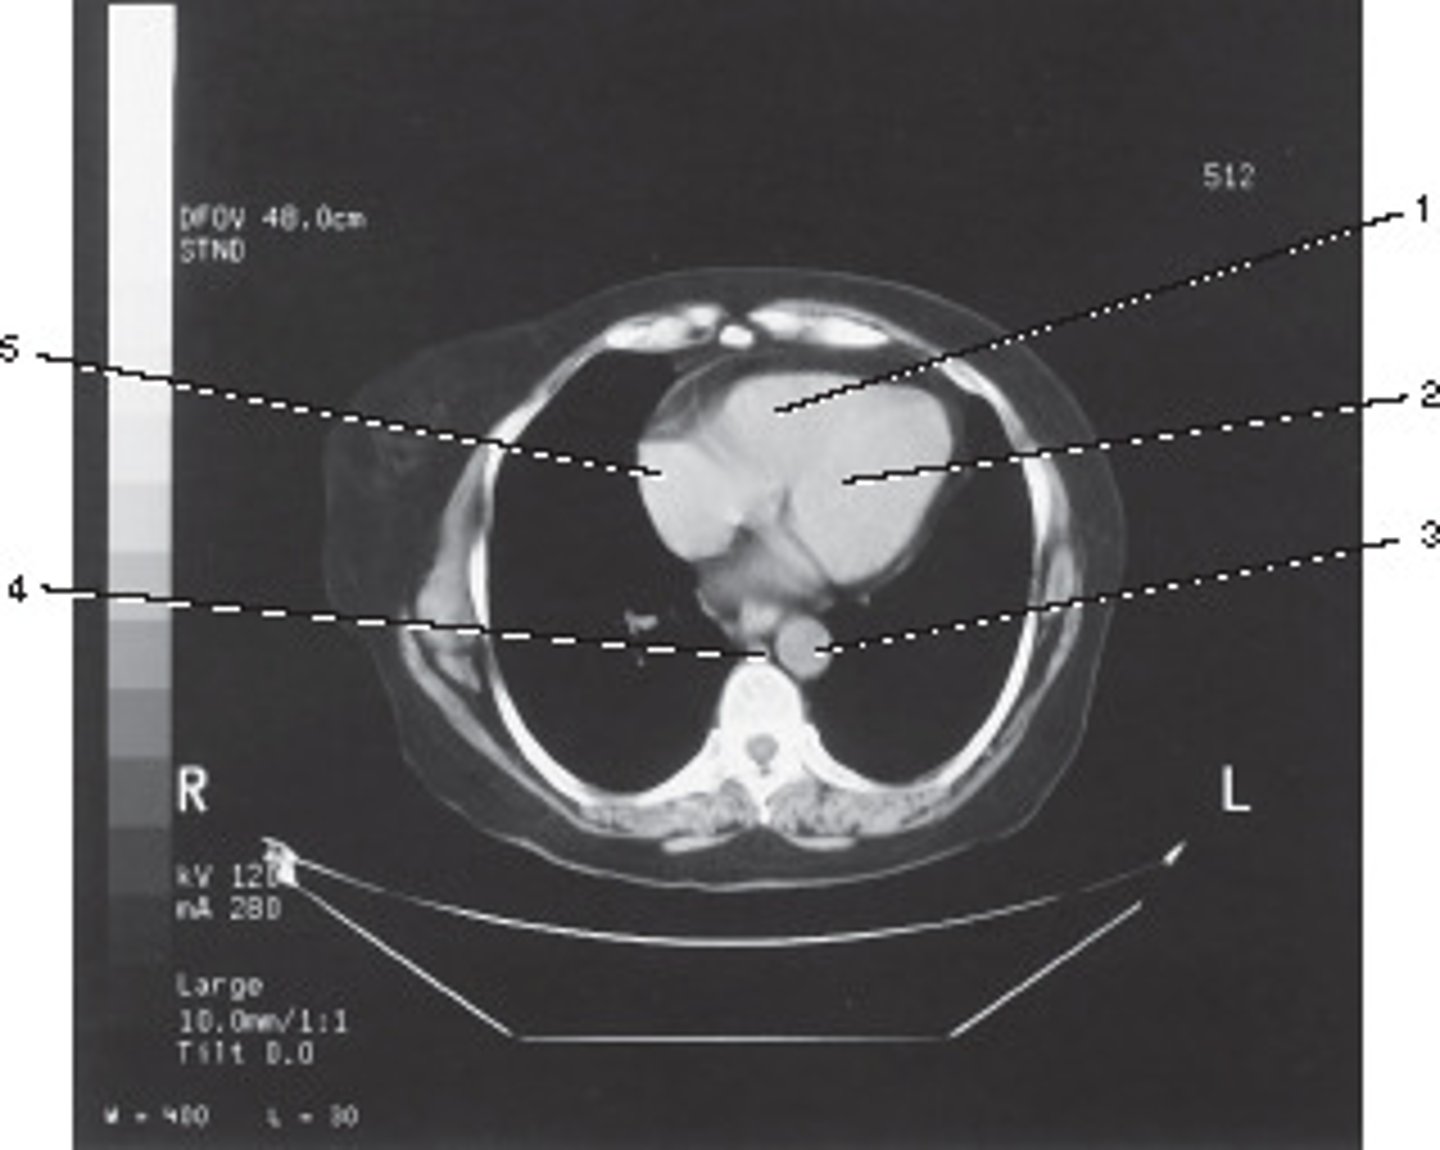

Which number corresponds with the right atrium?

<p>Which number corresponds with the right atrium?</p>

Aortic Arch

Number 2 corresponds to which of the following?

Azygous Vein

Number 4 corresponds to which of the following?

Right Brachiocephalic Vein

Number 6 corresponds to which of the following?

standard, 512, and 10.0 mm

What algorithm, matrix size, and section thickness were used for this image?

<p>What algorithm, matrix size, and section thickness were used for this image?</p>